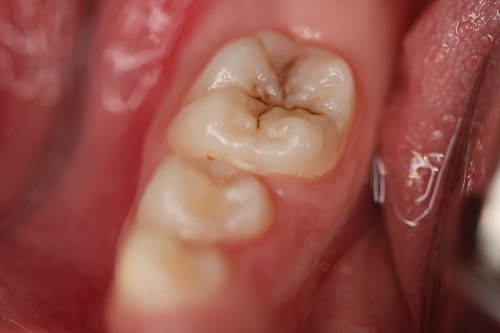

Materjal katab hambaarstiõppe vastava aine loenguteemad, tutvustades levinumaid suu- ja hambahaiguseid, kaariese tekkepõhjuseid ja kulgu ning mitmeid hamba kõvakudede patoloogiaid.